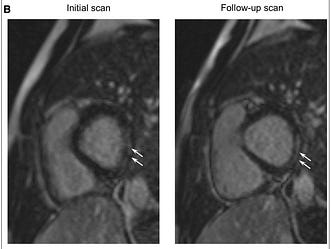

I saw one interesting thing this Saturday. A paper from a few weeks ago in Circulation looked at long term outcomes among young men with vaccine induced myocarditis. As predicted, some have residual scar.

Cardiologist, Anish Koka writes, “ The bad news: Small islands of scar could be substrate for future arrhythmias, that could be triggered by exercise. All these kids (even those without scar) would need exercise stress tests at 6 months to attempt to prognosticate this.”